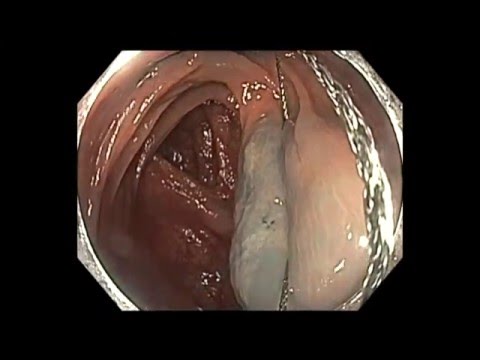

EMR poprzecznicy

U pacjenta w średnim wieku wykryto polipa okrężnicy poprzecznej, diagnoza wzrokowa - typ 2 wg klasyfikacji NICE. Po ostrzyknięciu polipa wykonano resekcję pętlową. Ranę po resekcji zabezpieczono za pomocą...